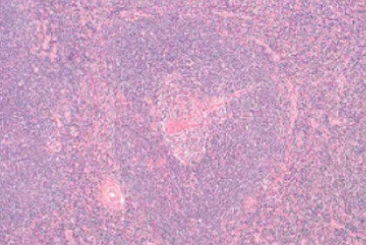

- starry sky pattern

- 星星:macrophages

- 夜空:核濃染的lymphoid cells其中的macrophage,其細胞質內含有apoptotic bodies

- 代表是high grade的lymphoma

- 兒童、年輕人

Burkitt lymphoma

- starry sky pattern